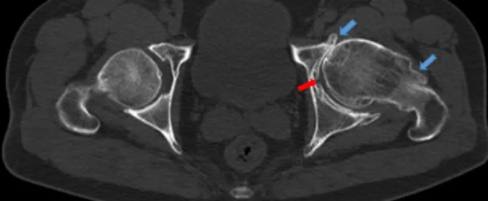

病例1-1 双髋关节轴位CT解剖结构

病例1-2 示双侧股骨头内沿皮质下走形的不规则线状高密度影硬化边,左侧股骨头中心密度弥漫性增高,内部呈低密度区,骨小梁结构模糊。